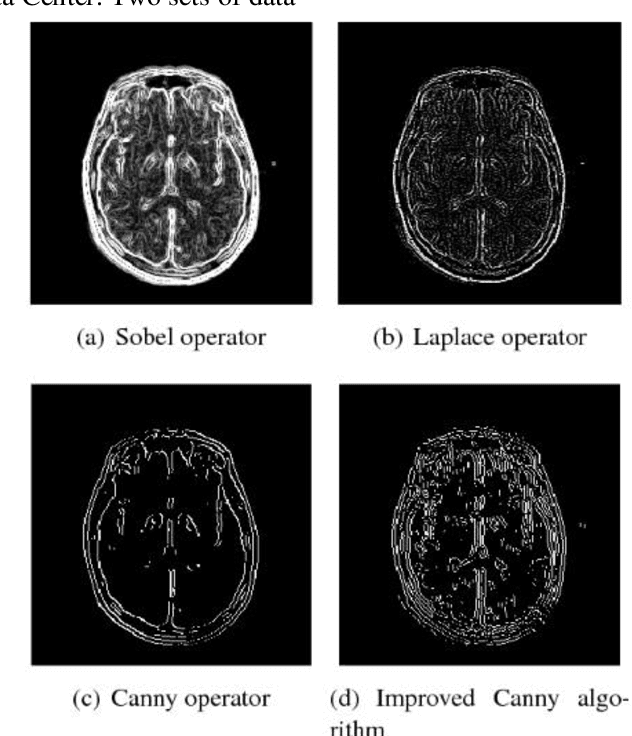

Abstract:Most of the existing wavelet image processing techniques are carried out in the form of single-scale reconstruction and multiple iterations. However, processing high-quality fMRI data presents problems such as mixed noise and excessive computation time. This project proposes the use of matrix operations by combining mixed noise elimination methods with wavelet analysis to replace traditional iterative algorithms. Functional magnetic resonance imaging (fMRI) of the auditory cortex of a single subject is analyzed and compared to the wavelet domain signal processing technology based on repeated times and the world's most influential SPM8. Experiments show that this algorithm is the fastest in computing time, and its detection effect is comparable to the traditional iterative algorithm. However, this has a higher practical value for the processing of FMRI data. In addition, the wavelet analysis method proposed signal processing to speed up the calculation rate.